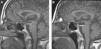

Un caso de hipopituitarismo y porfiria cutánea tarda por estrógenos en paciente con silla turca vacía

A case of hypopituitarism and porphyria cutanea tarda in relation to estrogen therapy in a patient with empty sella syndrome